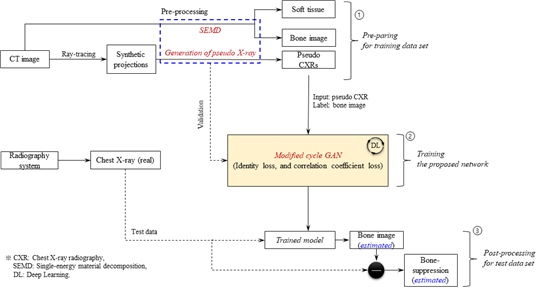

Background: Dual-energy (DE) chest radiography (CXR) enables the selective imaging of two relevant materials, namely, soft tissue and bone structures, to better characterize various chest pathologies (i.e., lung nodule, bony lesions, etc.) and potentially improve CXR-based diagnosis. Recently, deep-learning-based image synthesis techniques have attracted considerable attention as alternatives to existing DE methods (i.e., dual-exposure-based and sandwich-detector-based methods) because software-based bone-only and bone-suppression images in CXR could be useful.Purpose: The objective of this study was to develop a new framework for DE-like CXR image synthesis from single-energy computed tomography (CT) based on a cycle-consistent generative adversarial network.

Methods: The core techniques of the proposed framework are divided into three categories: (1) data configuration from the generation of pseudo CXR from single energy CT, (2) learning of the developed network architecture using pseudo CXR and pseudo-DE imaging using a single-energy CT, and (3) inference of the trained network on real single-energy CXR. We performed a visual inspection and comparative evaluation using various metrics and introduced a figure of image quality (FIQ) to consider the effects of our framework on the spatial resolution and noise in terms of a single index through various test cases.

- 연구소개

- 최근 연구에서는 기존의 이중 에너지(Dual-energy, DE) 흉부 방사선 촬영(CXR)을 대체할 새로운 프레임워크 개발에 주목하고 있습니다. 이 기술은 연조직과 뼈 구조를 선택적으로 영상화하여 다양한 흉부 병리(예: 폐 결절, 뼈 병변 등)를 더 정확하게 특성화하고, CXR 기반 진단의 개선 가능성을 모색합니다. 특히, 이번 연구는 단일 에너지 컴퓨터 단층촬영(CT)에서 DE와 유사한 CXR 영상 합성을 위한 새로운 프레임워크를 개발하는 것을 목표로 합니다. 이를 위해, AI 기반으로 한 프레임워크가 제안되었습니다. 제안된 프레임워크는 가상 CXR 생성부터 실제 단일 에너지 CXR에 대한 학습 및 추론까지, 세 가지 주요 기술로 구분됩니다. 연구 결과는 제안된 프레임워크가 소프트웨어 기반의 뼈 전용 및 뼈 억제 이미지를 CXR에서 유용하게 사용할 수 있는 대안으로서의 가능성을 보여줍니다. 이 연구는 특히 방사선 영상 분야에서 X-선의 선량 문제를 해결하고, 단일 노출로 가상 DE 영상을 가능하게 하는 새로운 방법론을 제시함으로써 의료 영상 진단의 질을 향상시킬 수 있는 유망한 접근 방식을 제시합니다.